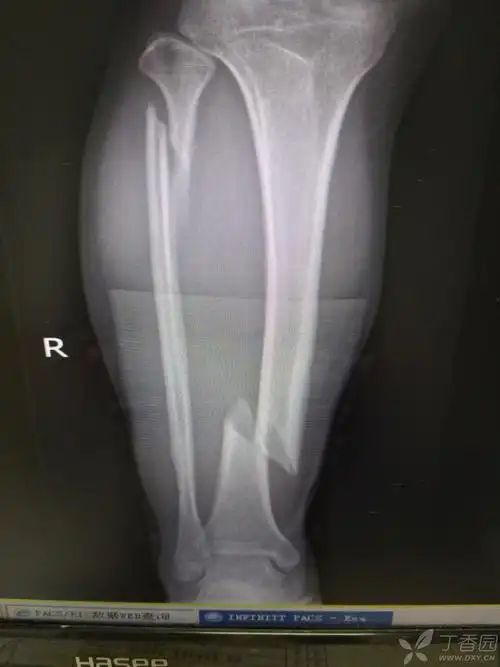

医学影像 摔伤致左小腿下段疼痛,活动受限,x线见腓骨骨折, - 抖音

谁来试试,这个骨折怎么治? [病例帖]

胫腓骨骨折是否该手术治疗

腓骨骨折轴(腿骨). 腿x线(2便士)照片